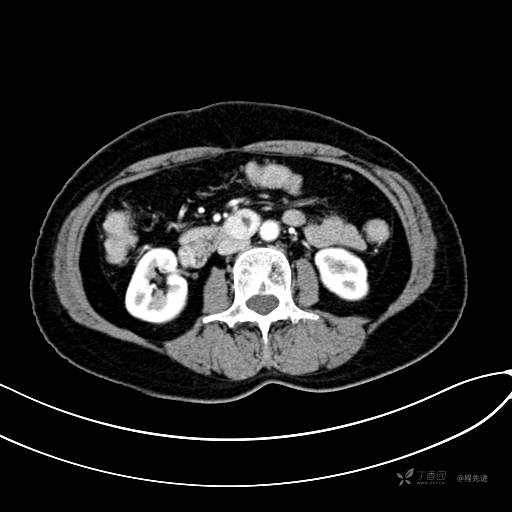

CT增强门脉期